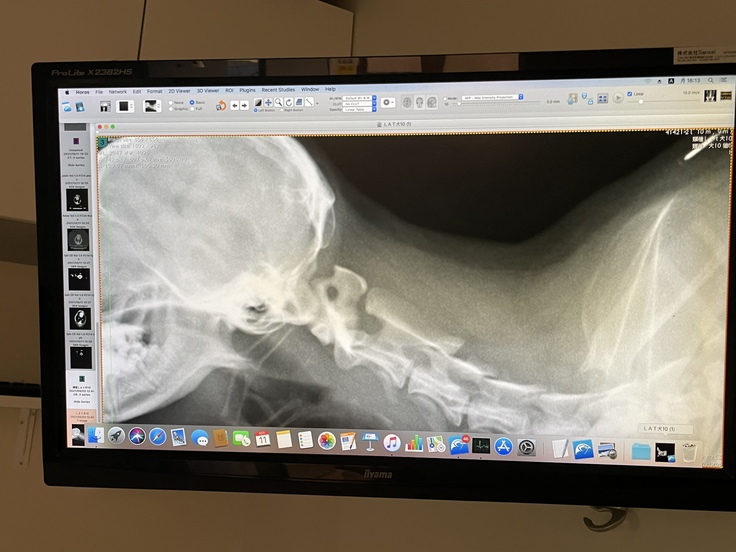

10月11日月曜日

本日手術に向けての第一歩のCTとMRの検査をうけてきました。

全身麻酔の為この日のために体重を増やしてきましたがわずか10gしか増えていませんでした。現在1.84kg

朝一番に入り検査の後は環軸椎不安定症の子は呼吸が不安定になり危険な事から夕方のお迎えになりました。

ドキドキで診察室へ行き、先生からの説明がありました。

やはり環軸椎不安定症で間違いないとのことでした。このような先天性の病気の子は他にも合併症が多いようですが幸いノアは合併症は見当たらず、そこだけは救いです。

青い丸の部分が通常は真っ直ぐに繋がっていますがノアはガクッと外れているのがわかりますよね。

このガクッとした部分にピンを入れてセメントで固める手術が今回ノアを救うための手術となります。

神経が通っている危険な場所なのでかなり難しい手術になるとは思います。